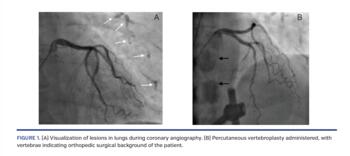

A 75-year-old female patient was admitted to the cardiology clinics with exertional dyspnea during daily activity. She had a history of diabetes mellitus and hypertension. Transthoracic echocardiography revealed normal ejection fraction, mild tricuspid regurgitation, and pulmonary hypertension (systolic pulmonary arterial pressure, 42 mm Hg). Coronary angiography was performed to rule out coronary artery disease. No significant lesion was found in the coronary arteries. However, some lesions were observed in the lungs during visualization of the coronary arteries. Based on the patient’s history and medical record, she had undergone percutaneous vertebroplasty for vertebral compression fracture 6 years prior. Following operation, pulmonary cement embolism had been developed due to the leakage of polymethylmethacrylate cement into the paravertebral venous plexus. Lesions seen on the lung area were interpreted as the late manifestation of the aforementioned complication (Figure 1A, white arrows; Video 1). Percutaneous vertebroplasty implemented vertebrae were also visualized by another coronary angiographic view demonstrating orthopedic surgical history of the patient (Figure 1B, black arrows; Video 2). After the coronary angiography, she was referred to pulmonary medicine department for further treatment.